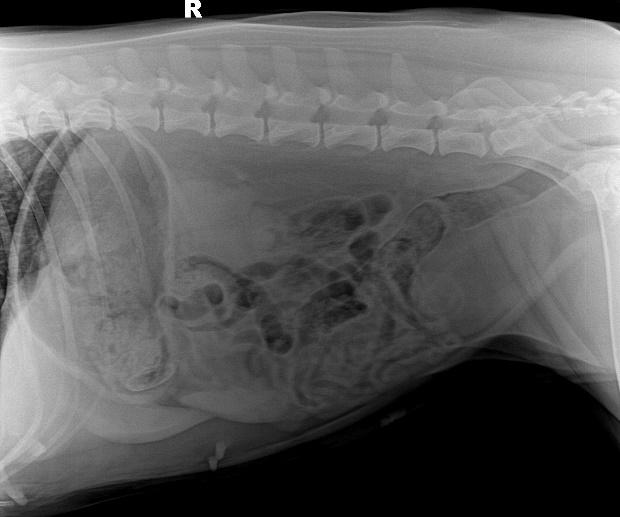

b. X射线检查:对于阻线性较强的物质(如金属、骨头)较容易辨别,对于阻线性与组织密度相似的物体较难确定,但是可以通过消化道灌服造影剂判断是否有阻塞或可包裹物体。

胃的正常大小:胃位于前腹部,隔和胆脏之后。胃排空时位于肋弓以内;从腹底算起,胃的腹侧缘大约在腹腔深度的1/3处。胃充盈时,胃向后向下延伸,与横结肠和腹底部相接。

摆位对

胃内异物(金毛,手术取出6cm大衣扣子)